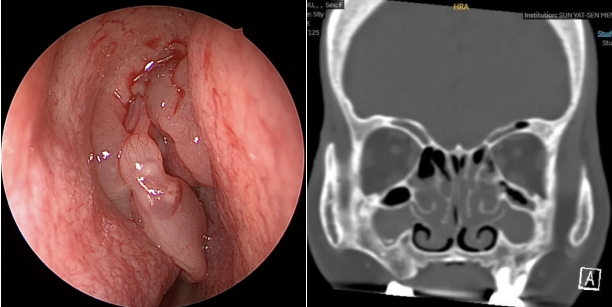

于是,阿云来到医院寻求帮助。刘教授详细询问了病情。阿云平时并没有鼻塞、流涕、头痛等症状,嗅觉问题近两年组建加重,偶尔能闻见一点气味。她并没有明确的外伤或上呼吸道感染史。体检中,并无发现鼻腔内有明显的异常,但嗅觉检测显示阿云的嗅觉中度损失。在其后的鼻内镜检查中,有了重要发现——在双侧鼻腔的最上部,也就是嗅裂区域,发现了息肉!刘教授告诉她,鼻息肉可能是导致她嗅觉下降的最大元凶。

深思熟虑后,阿云选择了手术治疗。术前的鼻窦CT检查,不出所料,阿云有全组鼻窦炎,尤其是筛窦炎。刘教授为她进行了微创手术-鼻内镜下鼻窦开放与鼻息肉切除术。术后,阿云恢复得很好,一周后就可以闻到气味了,一个月后阿云的嗅觉基本恢复到正常状态。

>>>刘教授小课堂

鼻腔嗅觉区域位于鼻腔的顶部(蓝色虚线方框圈出)非常狭窄的区域。当局部病变时,如局部肿胀、小息肉、局部分泌物等,可能并不影响呼吸、也没有鼻塞等症状,但嗅觉功能却有可能发生变化。正如阿云这个病例。虽然本病例经过手术等综合处理,患者嗅觉恢复了,但是患者还是要坚持复查与治疗,如生理盐水洗鼻、鼻喷激素等,日常预防感冒。若嗅觉再次下降一定要及时就医。